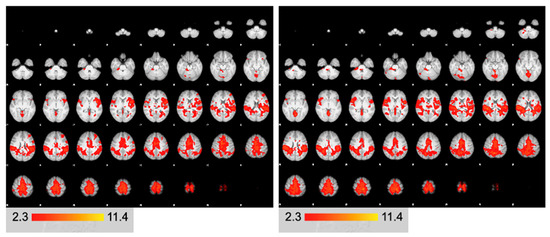

3. Results